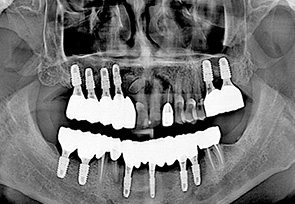

전악 임플란트는 치아가 완전히 없는 상태라도 잇몸뼈가 남아 있다면 임플란트를 여러개 심어 고정식으로 이를 해 넣을 수 있습니다. 잇몸 뼈에 단단히 고정되는 임플란트를 이용한 치료법으로 틀니를 사용할 때 보다 힘이 훨씬 좋고 내 치아 처럼 사용할 수 있습니다. 자연치아는 모두 28개 이지만 실직적으로 자연치아 개수만큼 다 심을 필요는 없습니다. 고정성 전악 임플란트를 위해서는 위 아래 턱 뼈와 맞물리게 되는 치아의 상태와 잇몸 뼈의 상태 등을 고려하여 임플란트를 식립하게 되며 보통 아래는 6~7개, 위에는 7~8개의 임플란트를 식립한 후 고정식으로 보철물을 결합하게 됩니다.

• before

• after